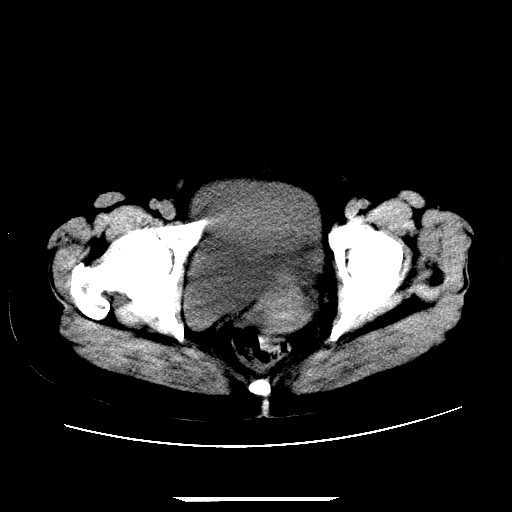

f,45y.怀孕4月晕倒,b超提示死胎,有手术结果,请展开讨论后明天告诉。

膈下-肠间隙内见气体密度影,子宫轮廓显示不清,宫腔-腹腔积液,首选考虑---子宫破裂出血。

1)宫腔妊娠。2)子宫破裂出血,腹腔及盆腔积血。

感谢同行们的高见。手术结果:子宫破裂出血。

我们的诊断是:腹、盆腔积液(考虑腹盆腔脏器破裂出血);宫腔妊娠。让人纳闷的是当时我们没有经验,现在回头看看分析:4月宫腔妊娠:1、洋膜囊不可能紧贴胎体这么小;2仔细看看子宫后壁肌层模糊不清;3腹、盆腔液体来源原因?4、45岁高龄妊娠有晕倒。由此可大胆诊断:宫腔妊娠子宫破裂出血。